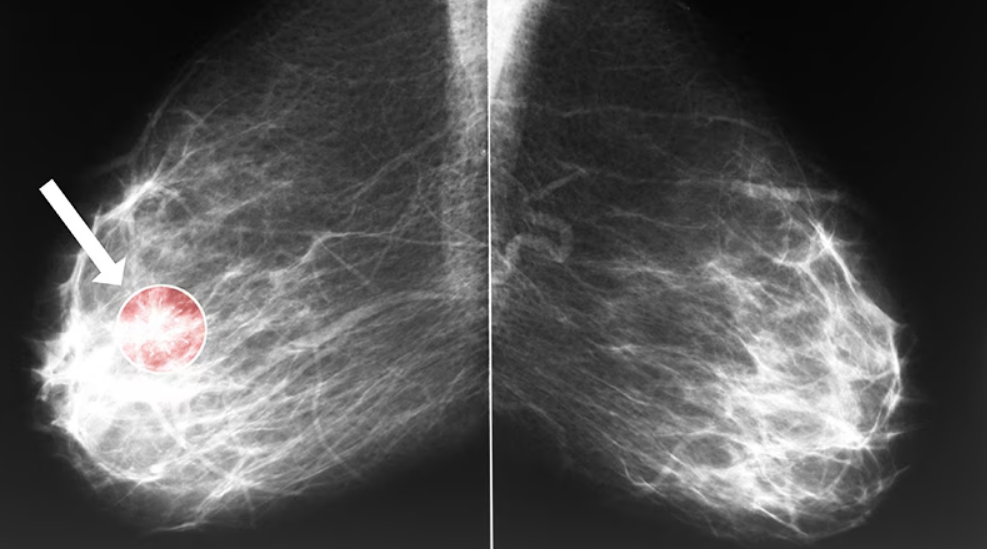

Cancer du sein : la radiothérapie peut endommager le coeur

Une récente étude américaine vient rappeler qu’un traitement vital n’est jamais dénué de risques.

Si la radiothérapie demeure un pilier incontournable dans la prise en charge du cancer du sein, les jeunes femmes traitées pour…